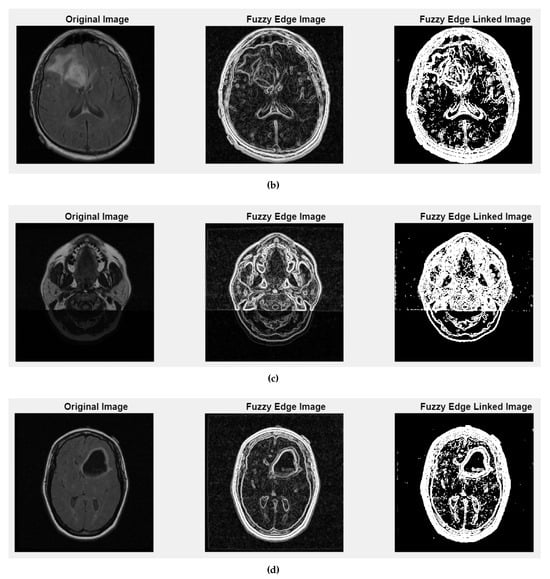

Figure 5 and Figure A2 illustrate the fuzzy edge detection approach in which Gaussian smoothing, gradient magnitude computation, and a fuzzy-inspired non-linear mapping are combined for the four case studies CS1, CS2, DU1, DU2. In each subfigure, the leftmost panels display the original (grayscale) scans, where the tissue boundaries naturally exhibit a degree of fuzziness due to partial volume effects, image noise, and inherent anatomical ambiguity. The middle panels present the application of fuzzy edge detection algorithms, which are specifically designed to preserve the uncertainty associated with boundary localization.

Unlike conventional edge detection methods that impose hard, binary edge definitions, these fuzzy approaches allow for gradual transitions and probabilistic boundary representations, which are particularly relevant for medical imaging contexts. The rightmost panels showcase the results obtained after applying fuzzy linked edge techniques. These methods focus on establishing connections between detected edge segments by considering similarity measures, spatial proximity, and continuity constraints. As a result, fragmented or weak edges are probabilistically linked, producing more continuous and visually coherent boundary structures while still preserving the underlying uncertainty.

Figure 4. Clustering with fuzzy C-means (FCM) results within iMIA platform: The clusters emphasize various structural and textural components, with some clusters isolating specific regions with clear edges and others focusing on more homogeneous areas. The segmentation reveals critical areas with varying intensity patterns, possibly indicative of different tissue types or pathological regions: TCGA_CS_4941_19960909_3 (CS1) (additional results are shown in Figure A1).

This progression from the original image to the fuzzy edge detection, and finally to the fuzzy-linked edge representation, reflects a complete processing workflow that supports both edge preservation and structural completeness. Such an approach is highly beneficial when analyzing complex medical images where exact boundary definitions are not always feasible and maintaining a degree of flexibility in edge interpretation is essential.

Figure A2. Fuzzy edge results from iMIA (Gaussian smoothing, gradient magnitude computation, a fuzzy-inspired non-linear mapping): (b) TCGA_CS_4941_19960909_14 (CS2), (c) TCGA_DU_5872_19950223_1 (DU1), (d) TCGA_DU_5872_19950223_35 (DU2). Leftmost image: original grayscale image; middle image: fuzzy edge; rightmost image: linked fuzzy edge (refer to the image (a) CS1 result in Figure 5).